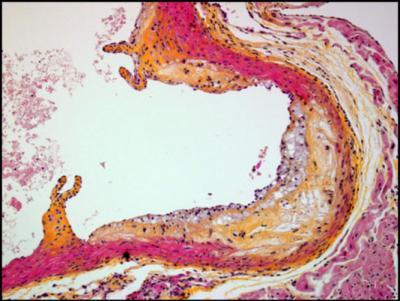

The research published today shows that the AT04A vaccine, when injected under the skin in mice that have been fed fatty, Western-style food in order to induce high cholesterol and the development of atherosclerosis, reduced the total amount of cholesterol by 53%, shrank atherosclerotic damage to blood vessels by 64%, and reduced biological markers of blood vessel inflammation by 21-28%, compared to unvaccinated mice. Furthermore, the induced antibodies remained functional over the whole study period and concentrations were still high at the end of the study.